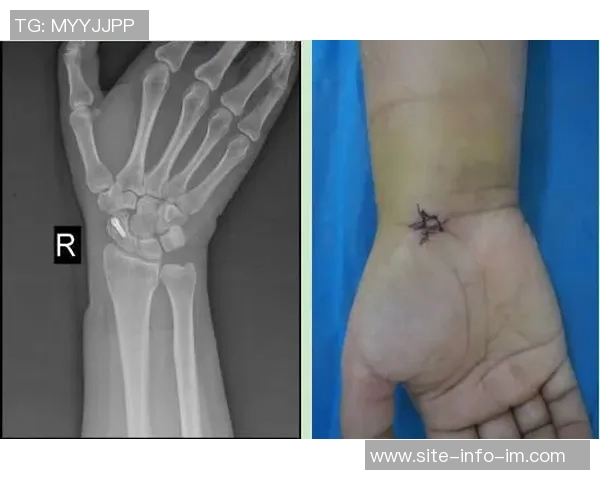

近日,国际米兰俱乐部官方宣布,球队后卫迪詹纳罗在比赛中不幸遭遇右手腕骨折,将接受手术治疗。这一消息令广大球迷感到震惊和惋惜,因为迪詹纳罗在球队中的表现一直备受期待。本文将从多个角度详细分析这一事件的影响及其对国米未来的意义,包括伤情对球队战绩的影响、球员恢复与手术前景、国米后防线的调整策略以及如何保持士气等方面,希望能为读者提供一个全面的视角。

关于迪詹纳罗即将接受手术治疗的信息,也引发了外界对于他恢复进程的广泛关注。一般而言,运动员在经历骨折后的恢复时间是相对漫长且充满挑战的。他需要进行详细检查以确保手腕骨折情况得到妥善处理。